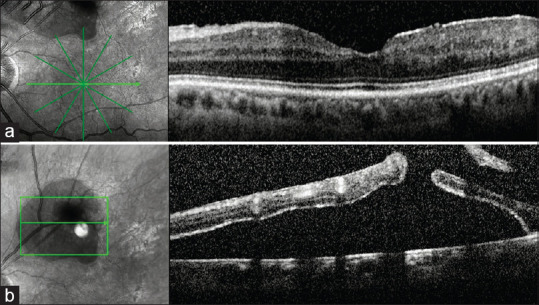

Resolution of the hole-related subclinical retinal detachment following barrage and sectorial laser photocoagulation in ischemic branch retinal vein occlusion.